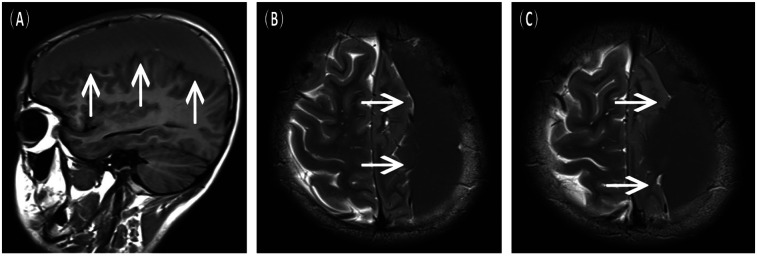

This case report discusses a 16-year-old male with a previously diagnosed left fronto-temporo-parietal arachnoid cyst (AC) who developed progressively worsening intermittent headaches. Magnetic resonance imaging (MRI) revealed a spontaneous chronic subdural hematoma (CSDH), despite no history of trauma or bleeding disorders. The cyst, discovered incidentally three years prior, had been asymptomatic until this event; hence, no interval cranial computed tomography (CT) or MR imaging was performed. The patient underwent burr-hole irrigation and drainage under general anaesthesia. Postoperative scans confirmed complete resolution of the hematoma and a significant reduction in the cyst size, with no recurrence of the cyst at the six-month follow-up. This case, supported by a systematic review of 28 recent studies (2020-2025), highlights that AC can spontaneously rupture, leading to CSDH. Burr-hole irrigation surgery proves to be a safe and efficient intervention, emphasizing the need for long-term monitoring in AC patients to manage potential hemorrhagic complications promptly.

Abstract Image